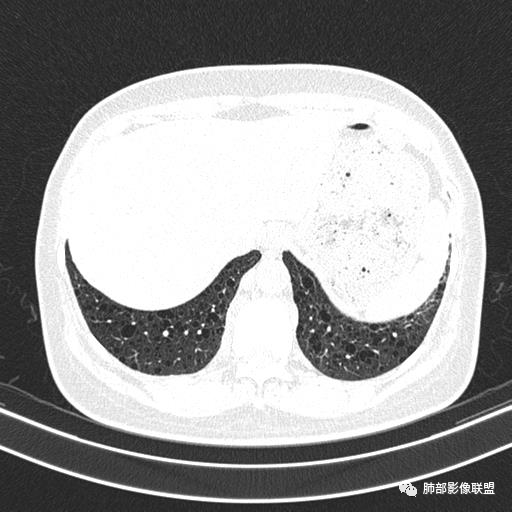

双肺弥漫囊腔,累及肋膈角,囊腔形态相对规则单一。

CT平扫示双肺弥漫分布大小不等囊状薄壁透光区,无内、中、外带分布差异,间质稍示增厚。拟LAM

女,46,活动性气喘1年。苯吸入史半年。胸部CT:两肺弥漫囊腔,上至肺尖,下至肋膈角,形态类似小囊腔。考虑:LAM,鉴别LIP,BHD,PLCH等。

CT表现:双肺弥漫大小不等的薄壁囊腔,囊壁<2mm,外形规则,血管影多位于囊腔周围,囊腔之间肺组织正常,随着疾病进展到晚期,囊腔变大、增多,不可胜数,囊腔可融合成较大的囊,与肺气肿相似,形成间质性肺纤维化。部分病例可出现结节影。